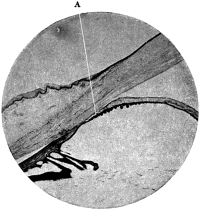

| 110. | The Normal Angle of the Anterior Chamber | 217 |

| 111. | The Angle of the Anterior Chamber from a Case of Recent Glaucoma | 218 |

| 112. | The Angle of the Chamber in a Case of Chronic Glaucoma | 219 |